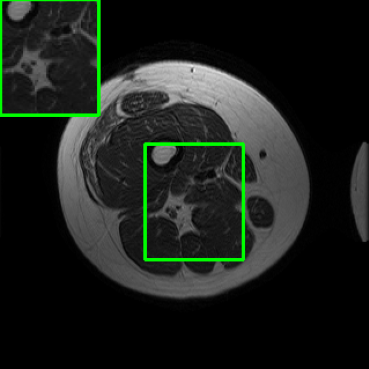

Performance on the Stanford FSE Dataset: We also performed image reconstructions with the Stanford multi-coil FSE dataset, which is a smaller dataset. We used same settings for the networks and training as in Section IV-A. Table III shows that LONDN-MRI significantly outperforms the globally learned MoDL network at both 4x and 8x acceleration. This indicates benefits for the proposed framework for smaller, more diverse datasets. Figs. 7 and 8 display visual comparisons that show the LONDN-MRI scheme recovering sharper features than the globally learned network.

| Ground Truth | Initial | Global | LONDN-MRI | LONDN-MRI | Oracle |

| (1 iteration) | (2 iterations) | ||||

![]() |

| PSNR = dB | PSNR = 22.01 dB | PSNR = 29.02 dB | PSNR = 31.46 dB | PSNR = 31.74 dB | PSNR = 31.87 dB |